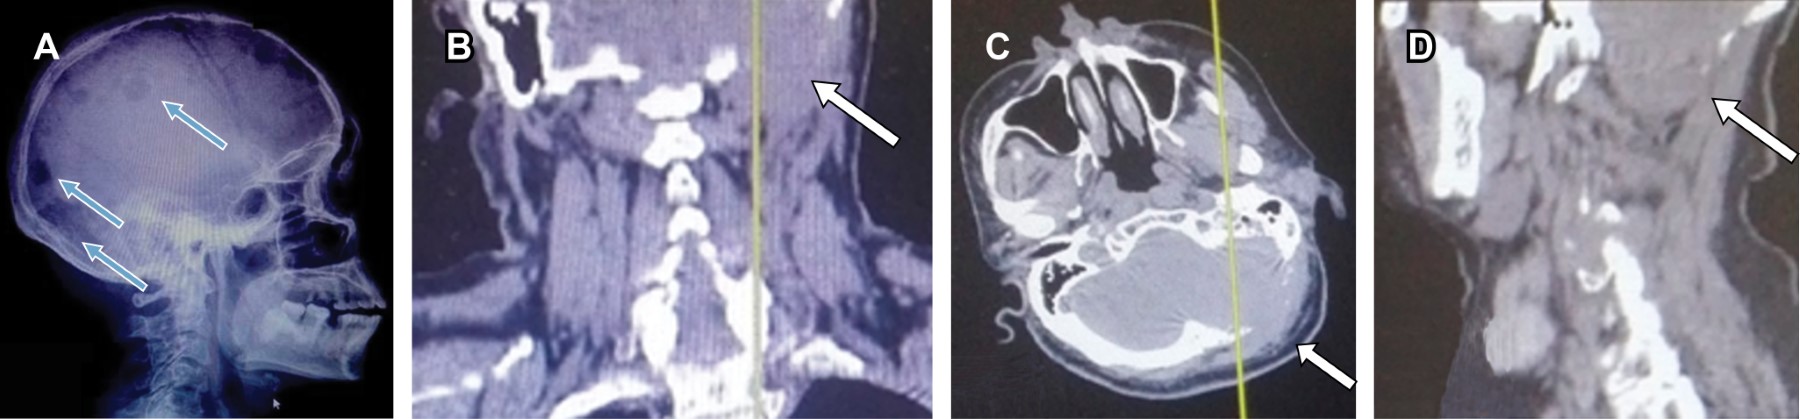

La distribución de las fracturas puede deberse a la infiltración de las células plasmáticas en el hueso trabecular similar al de la columna en comparación con el hueso menos hematopoyético como el cortical, lo que da como resultado la predilección de estas fracturas en regiones con mayor cantidad de trabéculas en su estructura (Figuras 1 y 2).11

Al analizar los síntomas de la enfermedad ósea al diagnóstico, se documentó que 9.1% (n = 3) de los pacientes tuvieron una fractura que presentaba características radiológicas de proceso neoplásico con sospecha y posterior diagnóstico confirmatorio de MM. Sin embargo, no todos los pacientes presentaban una fractura que sugiriera MM, algunos pacientes al momento del diagnóstico compartieron características clínicas de la EOMM, en las cuales encontramos: lumbalgia en 42.4% (n = 14), dolor óseo generalizado en 15.2% (n = 5), y 33.33% de los pacientes tenían un curso asintomático de la enfermedad (Figura 1).

Durante el seguimiento, se diagnosticaron 24 pacientes con alguna fractura asociada al mieloma múltiple, la localización de éstas se encontró con la siguiente distribución: columna en 39.4% (n = 13), húmero en 12.1% (n = 4), cadera en 9.1% (n = 3), fracturas con otra localización fuera del esqueleto axial en 9.1% (n = 3) y fémur en 3% (n = 1). Por otro lado, 27.3% de los pacientes no presentaron fracturas en el tiempo de seguimiento de este estudio.

Se realizó análisis de estudios de gabinete para encontrar datos radiográficos de la EOMM. De éstos, se excluyeron los hallazgos con trazo evidente de fractura, ya que varias características encontradas favorecerán la aparición de éstas, además de que denotan un estadio avanzado de la enfermedad. Al revisar los datos radiológicos de la enfermedad ósea encontramos que 30.3% (n = 10) de los pacientes presentaban lesiones líticas a nivel de la columna, la presencia de plasmocitoma se encontró en 18.8% (n = 8), lesiones líticas multinivel en 18.18% (n = 7) –estas lesiones incluyen más de un nivel vertebral, así como la inclusión de sacro o huesos largos–, destrucción vertebral en 6.1% (n = 2) y en 21.2% (n = 7) no se encontraron datos de enfermedad ósea del mieloma múltiple durante el seguimiento de los mismos.

El método radiológico de evaluación es relevante. En la literatura el más utilizado es la serie ósea metastásica, por lo que es el que utilizamos en nuestro hospital. Sin embargo, la capacidad de detección EOMM en pacientes al debut con este método fue sólo de 9%, aun cuando los pacientes referían sintomatología de la EOMM. Al realizar estudios complementarios a través del tiempo, se documentó la EOMM hasta en cerca del 80% de los pacientes. Esto obliga a buscar eventos relacionados al esqueleto con estudios de mayor sensibilidad como la tomografía o resonancia magnética o incluso PET SCAN/CT, ya que pueden identificarse lesiones más pequeñas y en etapas previas a fracturas.16